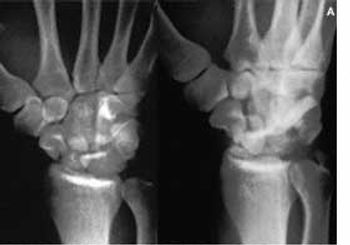

A 24-year-old man sustained a fall on his outstretched hand (FOOSH) injury that was complicated by wrist hyperextension. He complained of persistent right wrist pain and loss of grip strength.